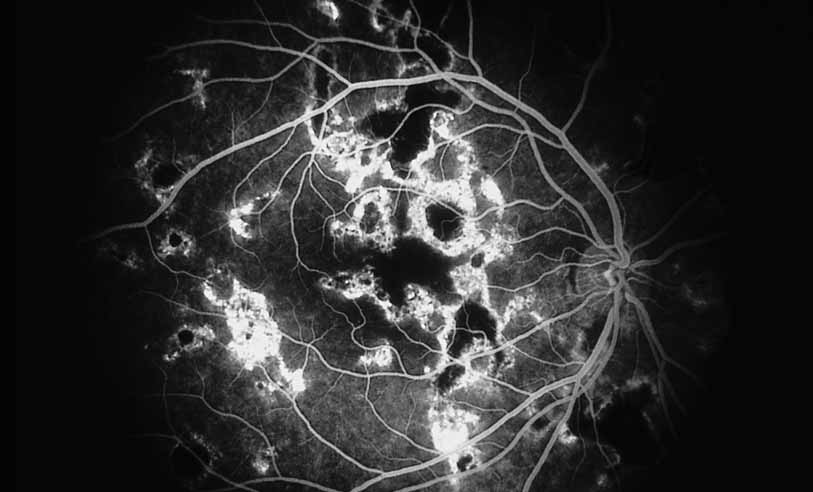

A third instance in which fluorescein angiography concentrating on the optic nerve may be helpful is in eyes with vascular engorgement of the optic nerve, especially with media opacities. Fluorescein angiography may help the clinician distinguish abnormally leaking capillaries from neovascularization. In acute multifocal hemorrhagic retinal vasculitis, optic nerve involvement is common in the early stages of the disease, 47 with optic nerve disc neovascularization seen later (see Figs. 10, 11, 12, and 13). Another fluorescein angiographic clue to the distinction between optic disc vessel engorgement and true neovascularization is the presence of associated large zones of retinal capillary nonperfusion such as those seen in sarcoidosis (see Figs. 14 and 15),34–40 acute multifocal hemorrhagic retinal vasculitis (see Figs. 10 and 11),47 or Eale disease (see Figs. 16 and 17).48–52

Ultimately, the diagnosis of optic nerve head neovascularization should be made on the angiographic characteristics of the optic nerve head vessels rather than on the presence of retinal capillary nonperfusion, because some patients, including those with severe forms of pars planitis or sarcoid, may develop “inflammatory” neovascularization in the absence of ischemia that responds to antiinflammatory therapy rather than scatter photocoagulation (see Fig. 18).

Fig. 18 Sarcoid disk neovascularization. An elderly woman with biopsy-proven sarcoidosis and chronic vitritis developed a vitreous hemorrhage in her right eye. Fluorescein angiography showed disk neovascularization without capillary nonperfusion.